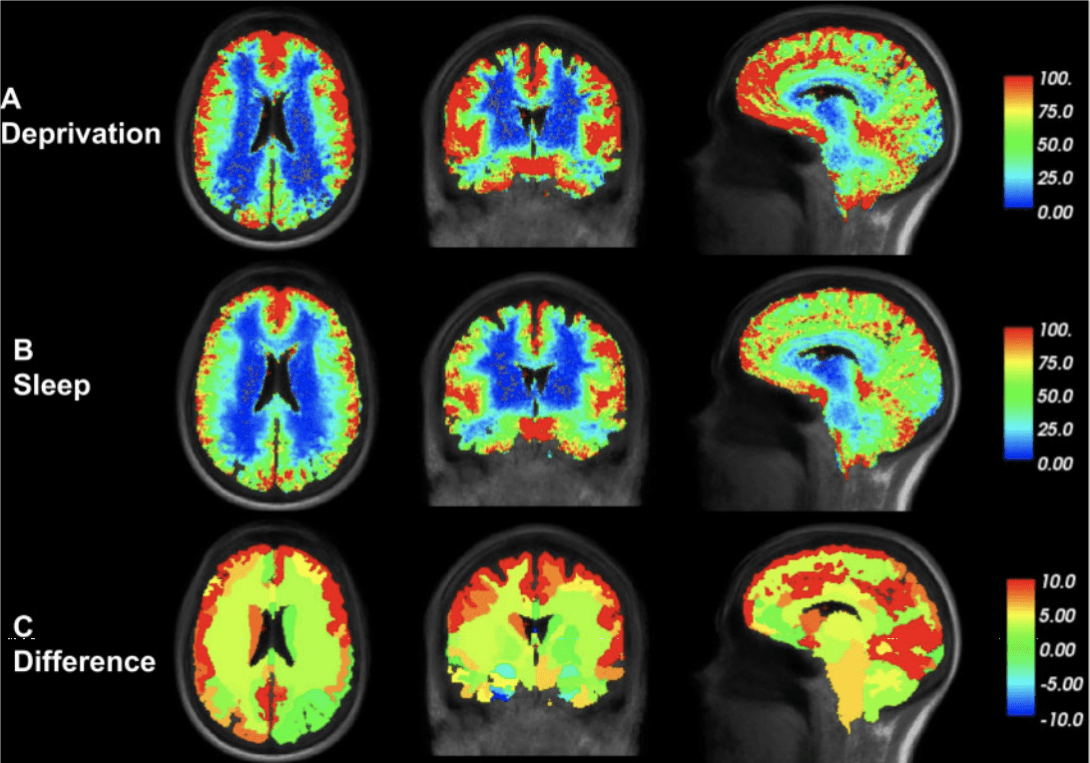

In patients who were not allowed to sleep one night, the study found a significantly higher proportion of tracer in the brain the next day than in those who were allowed to sleep. In the image above, the study shows the average increase in intensity on the MRI image (a marker for the proportion of tracer) for both the sleep and the sleep deprivation group. The last row shows the difference between the two groups, and all areas that are yellow or red here mean lower clearance of tracer in people who were not allowed to sleep.

The difference between the groups persisted for 48 hours, although both groups were allowed to sleep as normal the next night. It thus turns out that we can not catch up on lost sleep only with a subsequent good night's sleep.